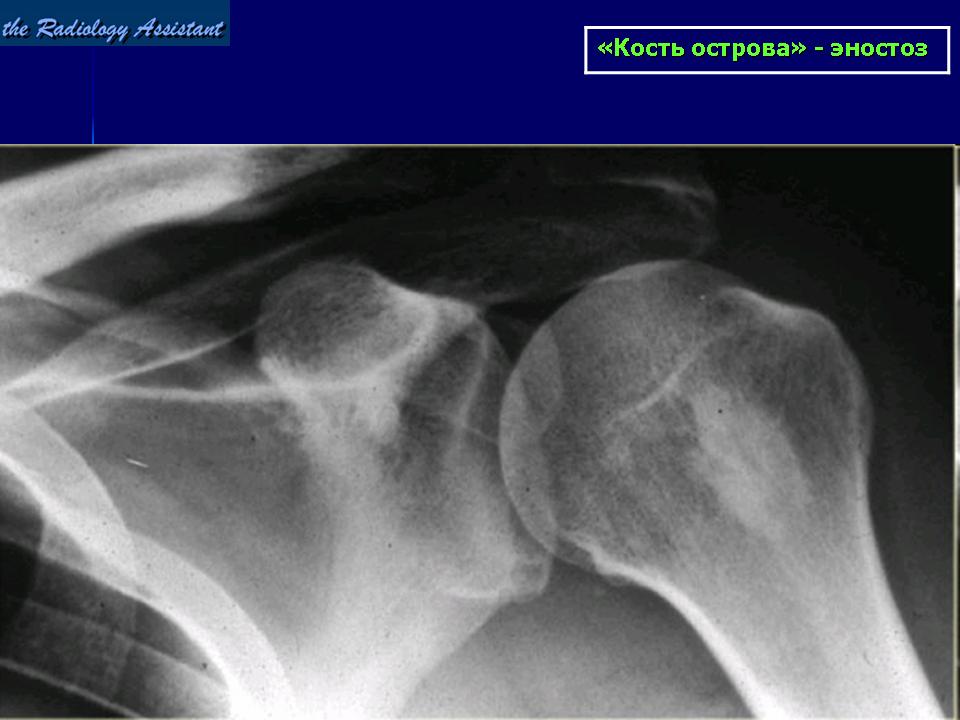

Эностоз кости: патогенез заболевания

Патология представляет собой доброкачественную опухоль, не склонную к быстрому росту и малигнизации. Эностоз или костный островок редко достигает размера более 2 см. В большинстве случаев заболевание не требует лечения. Для профилактики развития осложнений проводят контрольные обследования пациента 1-2 раза в год.

Для участков гиперостоза характерно увеличение объема и плотности костной ткани. Возрастает количество трабекул, расстояние между балочками сокращается. Образование имеет мелкопетлистую структуру. Разрастание компактного вещества кнутри от кортикального слоя носит название эностоз, кнаружи – экзостоз.

Поэтому подтвердить диагноз может только рентгенологическое обследование. С его помощью можно определить точную локализацию опухоли и ее форму.

Кроме того, именно с помощью рентгена можно точно установить диагноз благодаря тому, что эностоз сопровождается возникновением костных шипов вокруг опухоли. Также можно и уточнить доброкачественная опухоль или злокачественная, потому что доброкачественная всегда имеет четко очерченную форму.

Дифференциальная диагностика позволяет отличить образования в бедренной кости от ряда других заболеваний, например, асептических некрозов или склерозирующего остеомиелита. Узлы доброкачественного характера на рентгенограмме характеризуются однородной структурой и четко-очерченными краями.

В ситуации, если контуры размыты, у врача возникает подозрение на остеосаркому. Обструкция мозгового канала служит характерным признаком мраморной болезни. Заболевание многоочагового характера выявляется при губчатой остеоме: в том случае, если губчатое вещество характеризуется многоочаговым уплотнением структуры, это говорит о возникновении остеопойколии.